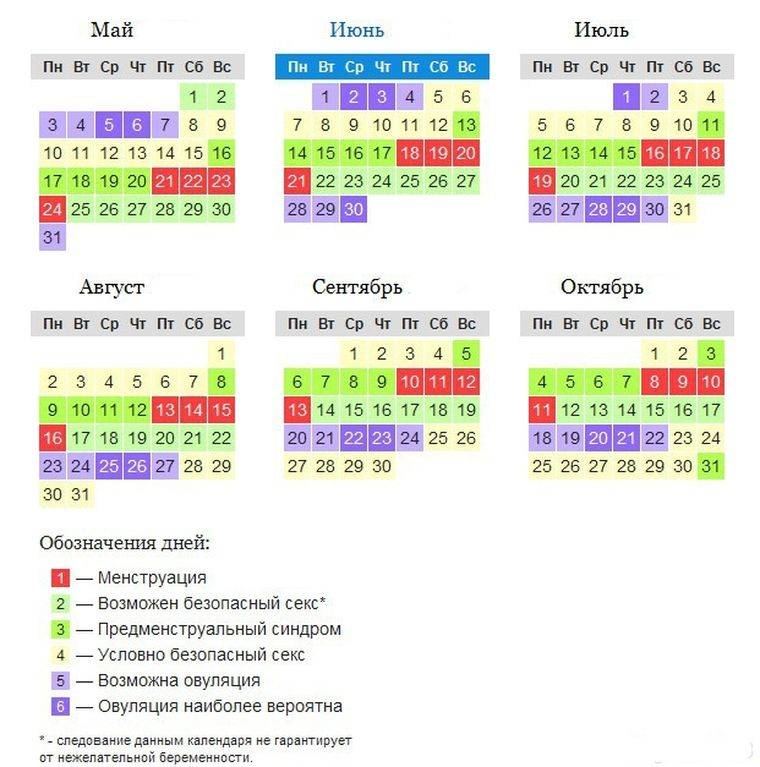

Рекомендации по зачатии